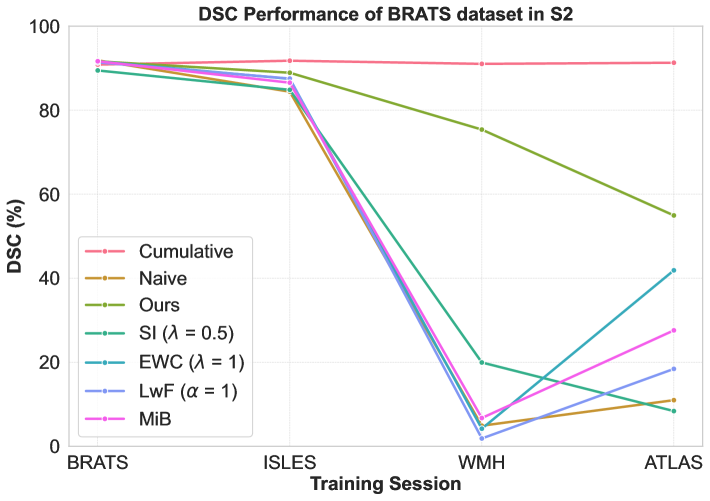

Performance comparison with others: For the considered medical applications, the primary concern will not be on improving zero-shot performance (FWT) but rather on minimizing forgetting (BWT) and enhancing the average DSC of the model (ACC and ILM). While FWT is reported for completeness, our analysis emphasize ACC, ILM, and BWT. Table 2 presents the ACC, ILM, BWT, and FWT values for all methods across sequences S1, S2, S3, and S4. Across all sequences, CL approaches (GDumb, Replay, MiB, LwF, SI, EWC, and the proposed method) mostly outperform naive training, highlighting the importance of mechanisms to mitigate catastrophic forgetting in UNet-based segmentation tasks. Further, as expected, approaches storing past data partially (Replay, GDumb) or fully (cumulative, joint training) show higher performance compared to methods (naive, MiB, LwF, SI, EWC, and the proposed approach) with no access to past exemplars. When comparing the proposed method to other buffer-free approaches (MiB, LwF, SI, EWC), it consistently achieves superior performance in all the sequences S1, S2, S3, and S4. Unlike these existing CL methods, which penalize large deviations from previously learned weights through response-level regularization terms in the training loss, the proposed approach introduces a drift-based dynamic penalization factor along with a latent-level regularization. This drift-based dual distillation allows for more effective mitigation of catastrophic forgetting. The proposed method shows a positive gain in (ACC, ILM, BWT) over best performance achieved among state-of-the art buffer-free approaches (blue colored in Table 2). Specifically, we observe an improvements of (25.51%, 9.23%, 34.34%) in S1, (6.57%, 25.28%, 31.85%) in S2, (4.85%, 11.02%, 40.15%) in S3, and (7.67%, 10.65%, 17.62%) in S4. For intuitive visualization, radar plots for S1, S2, S3, and S4, comparing cumulative, naive, the best-performing buffer-free methods, and the proposed approach are provided in Fig. 6 of Appendix.

Performance of a dataset in different sessions: We closely analyze CL model’s performances on first/second dataset upon learning other datasets in a given sequence. Specifically, Figure 3 shows DSC for BRATS in S1 and S2, ISLES in S3, and WMH in S4, with cumulative training included for reference. While cumulative training offers stable results, it requires access to all previous datasets, which is impractical in real-world scenarios. The naive approach shows significant DSC degradation, with high standard deviations of 33.91 (S1) and 40.23 (S2), 26.31 (S3), and 24.78 (S4) reflecting instability. In contrast, our CL strategy maintains stability, with much lower standard deviations of 5.19 (S1), 14.51 (S2), 11.37 (S3), and 15.50 (S4) highlighting its increased robustness against forgetting. Other buffer-free CL methods (MiB, SI, EWC, LwF) show better performance than naive training (Table 2) but still exhibit instability in DSC, with standard deviations of (28.80, 17.86, 31.14, 25.98) for S1, (36.75, 36.75, 35.85, 40.10) for S2, (25.43, 23.51, 25.65, 25.11) for S3, and (25.06, 15.51, 22.84, 23.55) for S4. While these methods perform well for natural images, their effectiveness is limited in brain MRI segmentation under domain shifts. In contrast, our approach delivers better stability and mitigates catastrophic forgetting effectively. Detailed segmentation visualizations for BRATS are provided in Appendix A.

Impact of dataset orders: We study the impact of different sequences on overall performance. We analyze ACC, ILM, BWT by best performing other CL methods and proposed approach for S1-S4 in Table 2 (summarized in Table 4, Appendix). We can see that best ACC is poor in S2 (28.54) and S3 (35.85) as compared to that in S1 (54.31) and S4 (50.67). Notably, all methods (except EWC) showed performance degradation when ATLAS (a single-modality dataset) was introduced later in sequences (S2, S3), adversely impacting the generalization of previously acquired knowledge in the model. This occurs because “modality dropping”, a critical generalization technique, cannot be applied to ATLAS due to its single-modality nature. Consequently, learning ATLAS in the later stages negatively impacts the model’s prior generalization capability. In contrast, when we learn datasets with fewer modalities at the start of sequences (S1 and S4), their negative effect is covered at later stages when we learn datasets with more modalities.